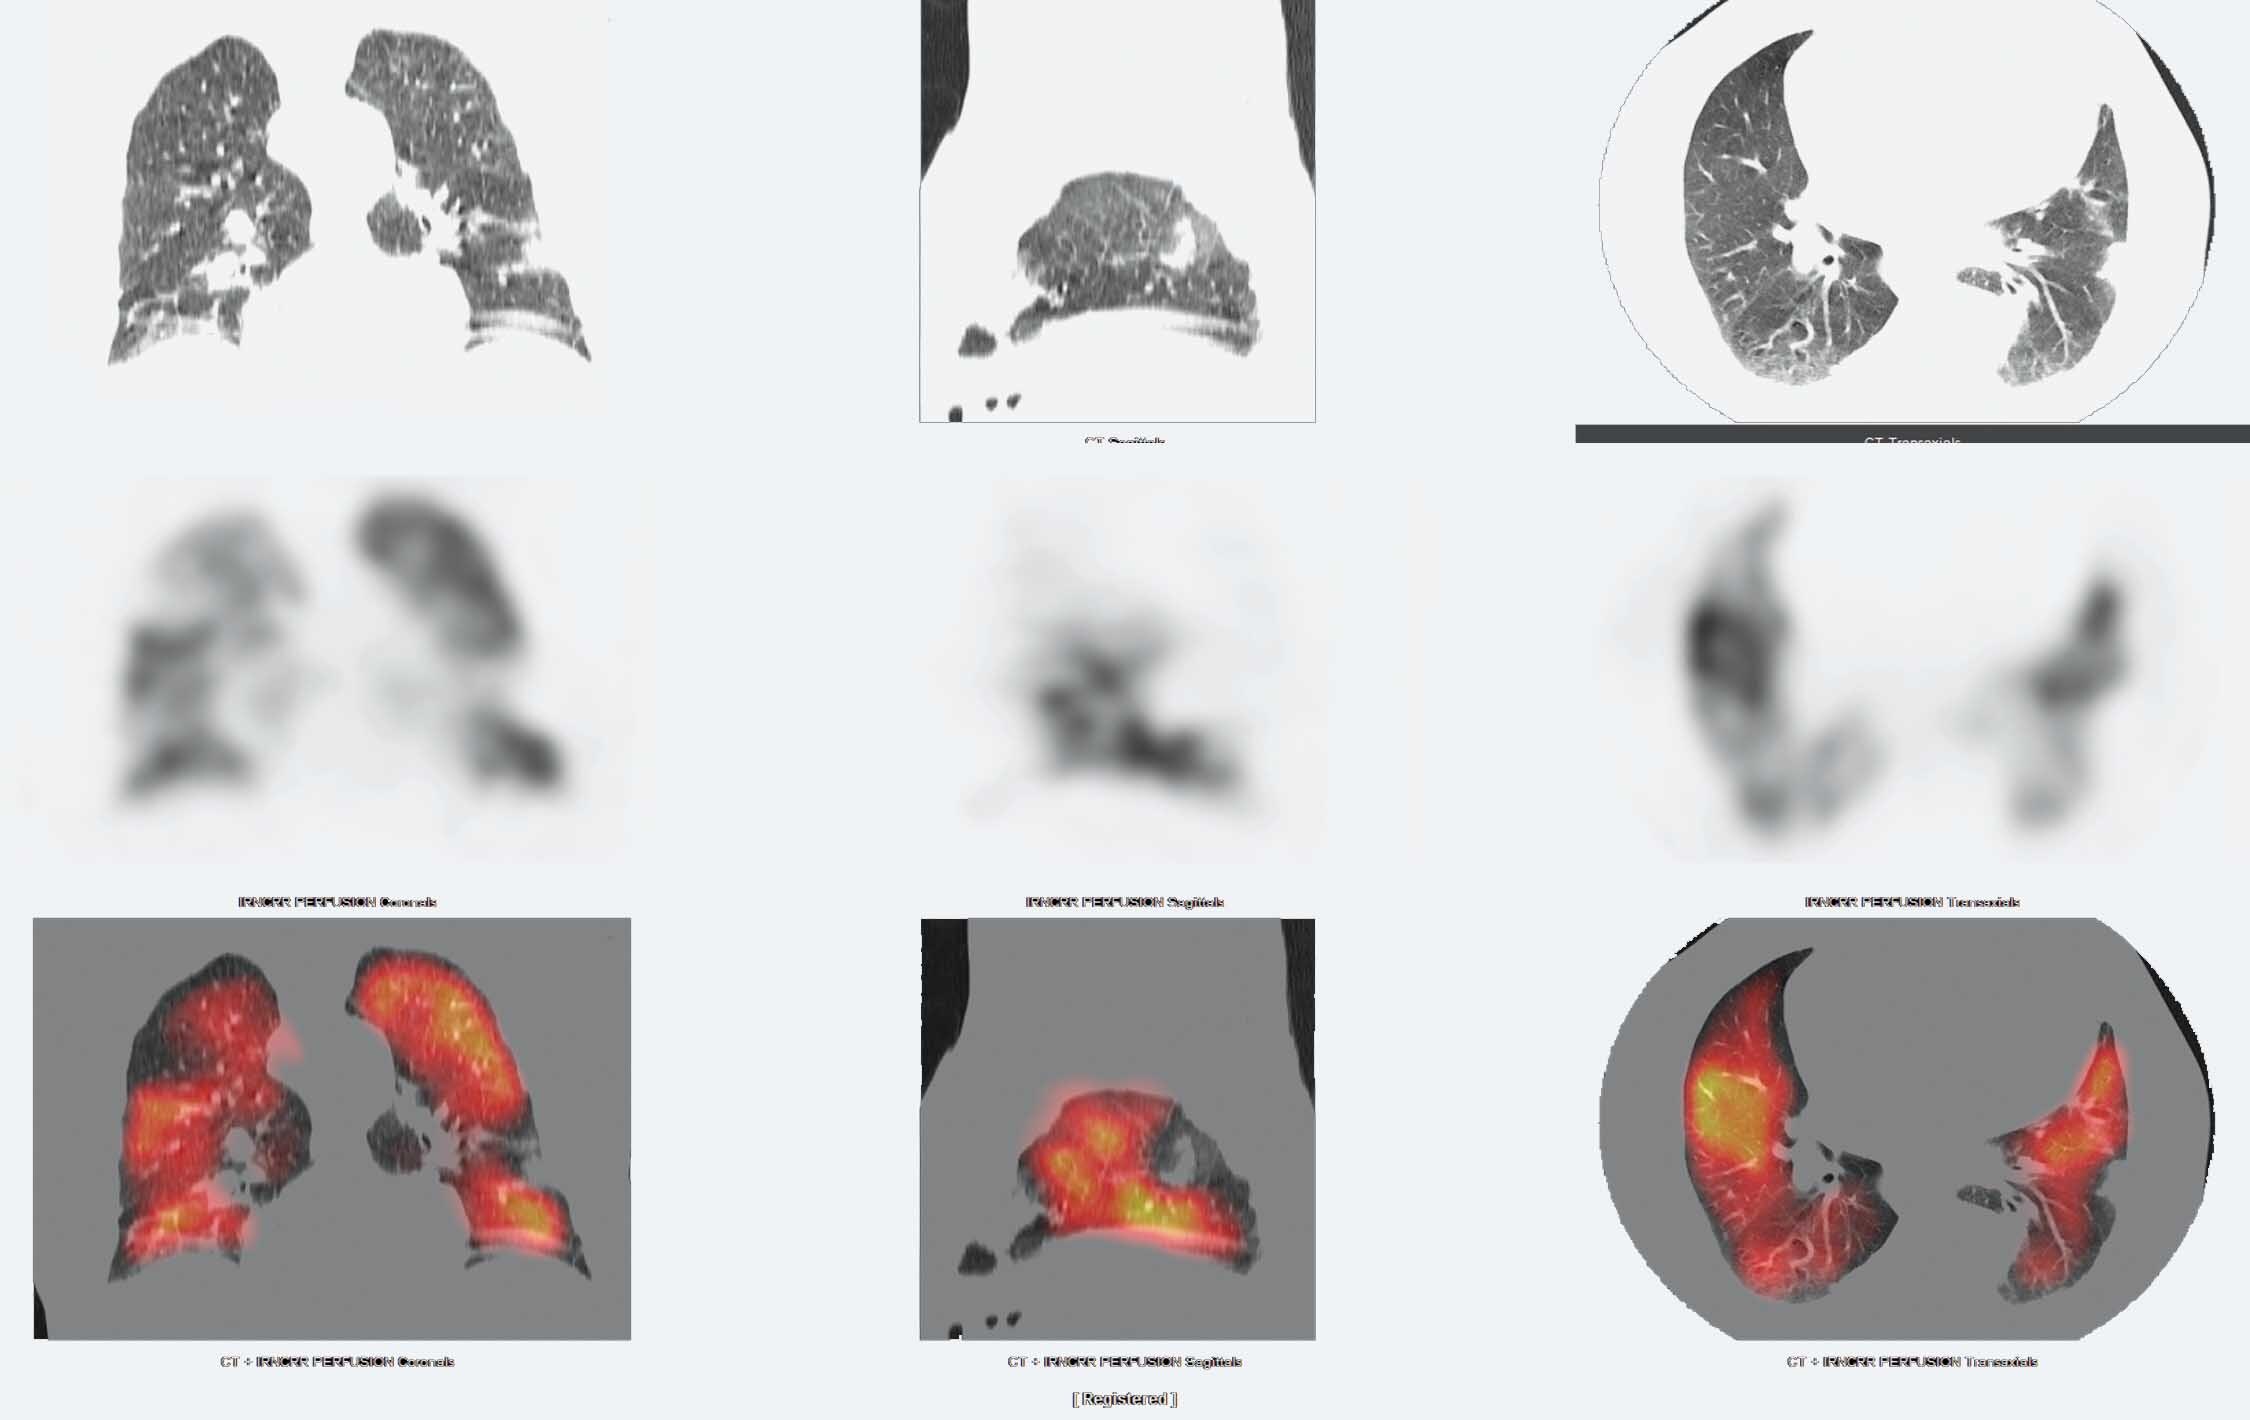

VQ SPECT/CT in the follow up of recovered COVID19 patients, with

V/Q SPECT and SPECT/CT in Pulmonary Embolism Journal of Nuclear Spect V/Q Scan It can help diagnose lung conditions, such as blood. learn how to perform and interpret v/q scans for various clinical applications, including evaluation of pulmonary embolism. a vq scan assesses blood supply and aeration to your lungs using radioactive material and a gamma camera. It can help diagnose lung. any nuclear medicine department equipped with a modern. Spect V/Q Scan.

(PDF) The Added Value of LowDose CT to SPECT V/Q Scan in Diagnosis of Spect V/Q Scan It can help diagnose lung. It can help diagnose lung conditions, such as blood. a vq scan assesses blood supply and aeration to your lungs using radioactive material and a gamma camera. the authors review the role of v/q imaging in evaluation of acute and chronic pulmonary. any nuclear medicine department equipped with a modern hybrid scanner. Spect V/Q Scan.

FIGURE 3. Tomographic Imaging in the Diagnosis of Pulmonary Embolism Spect V/Q Scan It can help diagnose lung. a vq scan assesses blood supply and aeration to your lungs using radioactive material and a gamma camera. the authors review the role of v/q imaging in evaluation of acute and chronic pulmonary. any nuclear medicine department equipped with a modern hybrid scanner can now perform combined v/q spect with ct (using. Spect V/Q Scan.